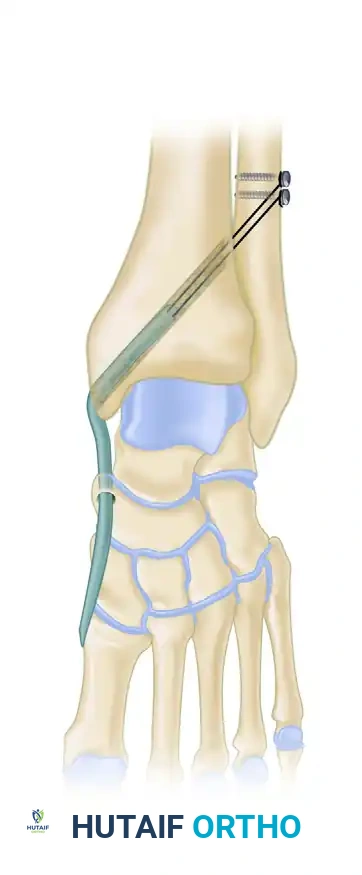

If the spring ligament is severely attenuated, a reconstruction using a peroneus longus autograft tendon transfer may be performed. The medial soft tissues are prepared, and bone tunnels are drilled, but final tensioning is delayed until after the lateral column lengthening is complete to avoid tearing the medial repair during lateral distraction.

Figure 1: Reconstruction of the spring ligament using a peroneus longus autograft tendon transfer. Lateral view demonstrating the calcaneal bone tunnel reconstruction.